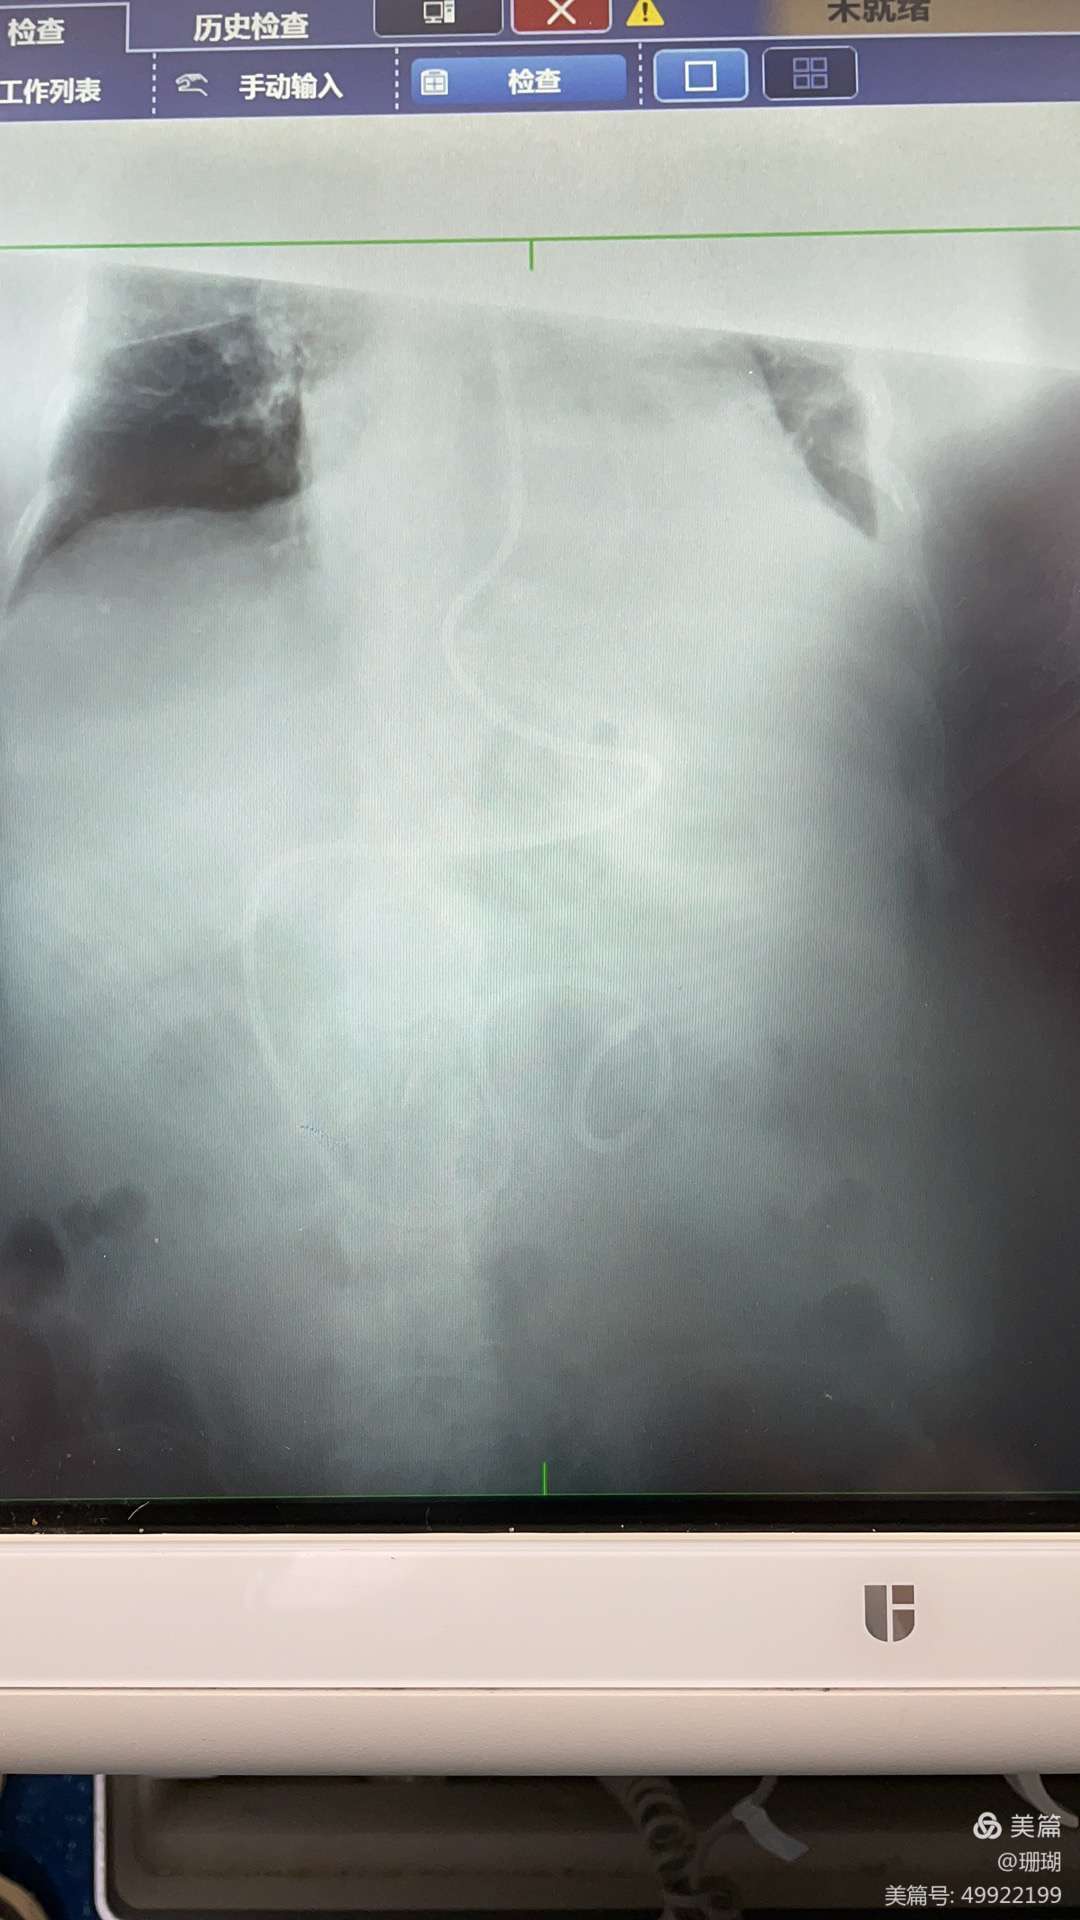

经过前期的准备工作,在江榕老师的指导下,我院ICU护士长刘思思与责任护士吕思琪相互协作,有条不紊、配合默契,通过听诊判断管端的位置是否正确,固定稳妥后通过X线确诊操作顺利完成。